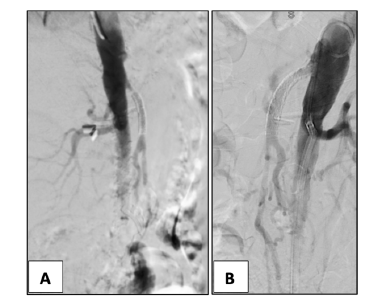

In two patients, proximal SMA stenosis was treated with proximal extension with a covered stent, Figure 2. One patient with SMA stenting stenosis was submitted to SMA angioplasty with a DCB and CT stenting with a covered stent, Figure 3. In one patient with SMA stent reocclusion, a two-vessel revascularization with aorto-mesenteric bypass and IMA re-implantation was performed due to IMA ostial high-grade stenosis and previous evidence of an incomplete right aorta’s arch. Thirty-day and 3-year overall survival in the OR and ER groups were 67% vs. 93% and 44% vs. 87%, respectively (p=.015, Figure 4).

Figure 3 Intra-operative angiography of a restenosis case after SMA stenting (case 2). Proximal stent stenosis (A) dilated with a drug-eluting balloon 6x40 mm (B). CT high-grade stenosis (C) treated with a covered stent Advanta 7x22mm (D).